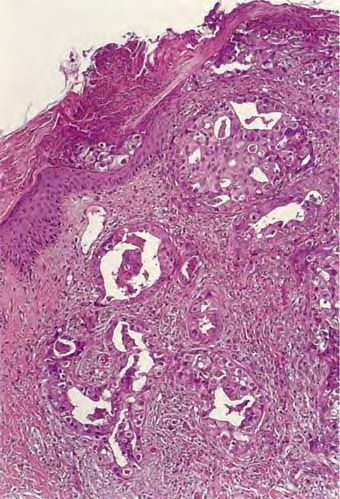

metastasis